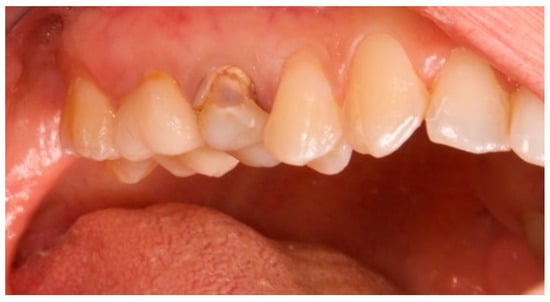

Figure 1.

Vestibular view prior to implant insertion of tooth 1.5.